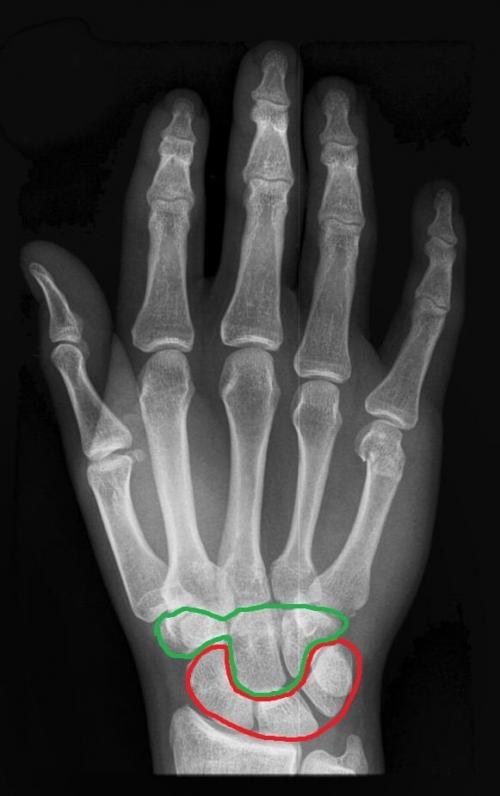

А теперь давайте сориентируемся на настоящем рентгеновском снимке и попробуем на нём найти проксимальный и дистальный ряды костей запястья (цвета такие же):

Проксимальный ряд костей запястья:

- Ладьевидная кость (os scaphoideum) . Эта кость занимает самое латеральное (самое «лучевое») положение из всех костей проксимального ряда. Также ладьевидная кость является самой крупной костью проксимального ряда. Не перепутайте её с костью-трапецией из дистального ряда, о которой речь пойдёт чуть ниже. Чтобы не случилось такой путаницы, сначала научитесь различать проксимальный и дистальный ряды, а затем уже отдельные кости;

- Полулунная кость (os lunatum) . Дистальная поверхность этой кости очень вогнутая. Именно поэтому она выглядит как половина луны. Правда, это не особо заметно, когда вы рассматриваете всю кисть целиком. Намного лучше эта особенность строения различима, когда вы рассматриваете полулунную косточку отдельно. На препарате вы её можете найти сразу после ладьевидной кости — полулунная кость очень плотно примыкает к ней с медиальной стороны;

- Трехгранная кость (os triquertum) . Название трёхгранной кости также очень характерно — если вы рассмотрите эту кость отдельно, вы отчётливо увидите три грани. Трёхгранная кость занимает самое медиальное (самое «локтевое») положение из всех костей проксимального ряда;

- Гороховидная кость (os pisiforme) . Эта кость — самая маленькая из всех костей запястья. Она очень плотно сочленяется с трёхгранной костью, поэтому вы легко отыщите гороховидную кость, если найдёте самую медиальную кость проксимального ряда (то есть трёхгранную).